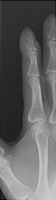

Also called a dropped finger, this injury results from hyperflexion to the distal interphalangeal joint. There is a dorsal avulsion fracture of the base of the distal phalanx. This indicates that the common extensor tendon remains attached to this avulsed fragment. The injury is typical at the second digit as the result of forced hyperflexion (catching a ball).

- Click on the image for a larger versionAOblique radiograph of the second digit. This demonstrates an avulsion fracture of the dorsal aspect of the distal phalanx.